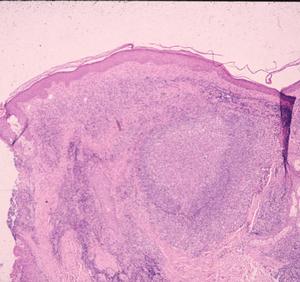

Patients in Europe have been seen with a lesion of skin referred to as Borrelia lymphocytoma or lymphadenosis benigna cutis, usually involving the ear lobe, lateral neck skin, or areola of the nipple. The histology is instantly recognizable by a marked dermal infiltrate of lymphocytes and other mononuclear inflammatory cells totally, or nearly totally replacing the dermis, with well-formed germinal centers (Fig. 3), as seen in lymph nodes or tonsillar lymphoid tissue, hence the term lymphadenosis. This is a remarkable lesion clinically and pathologically and is not always caused by Borrelia infection. When it is, however, the clinician should look for the spirochetes, which can be seen by silver stains. Other examples of early disseminated infection, which may be seen days to weeks following tick bite, include meningitis, radiculoneuritis, encephalopathy and Bell's palsy.

Figure 3